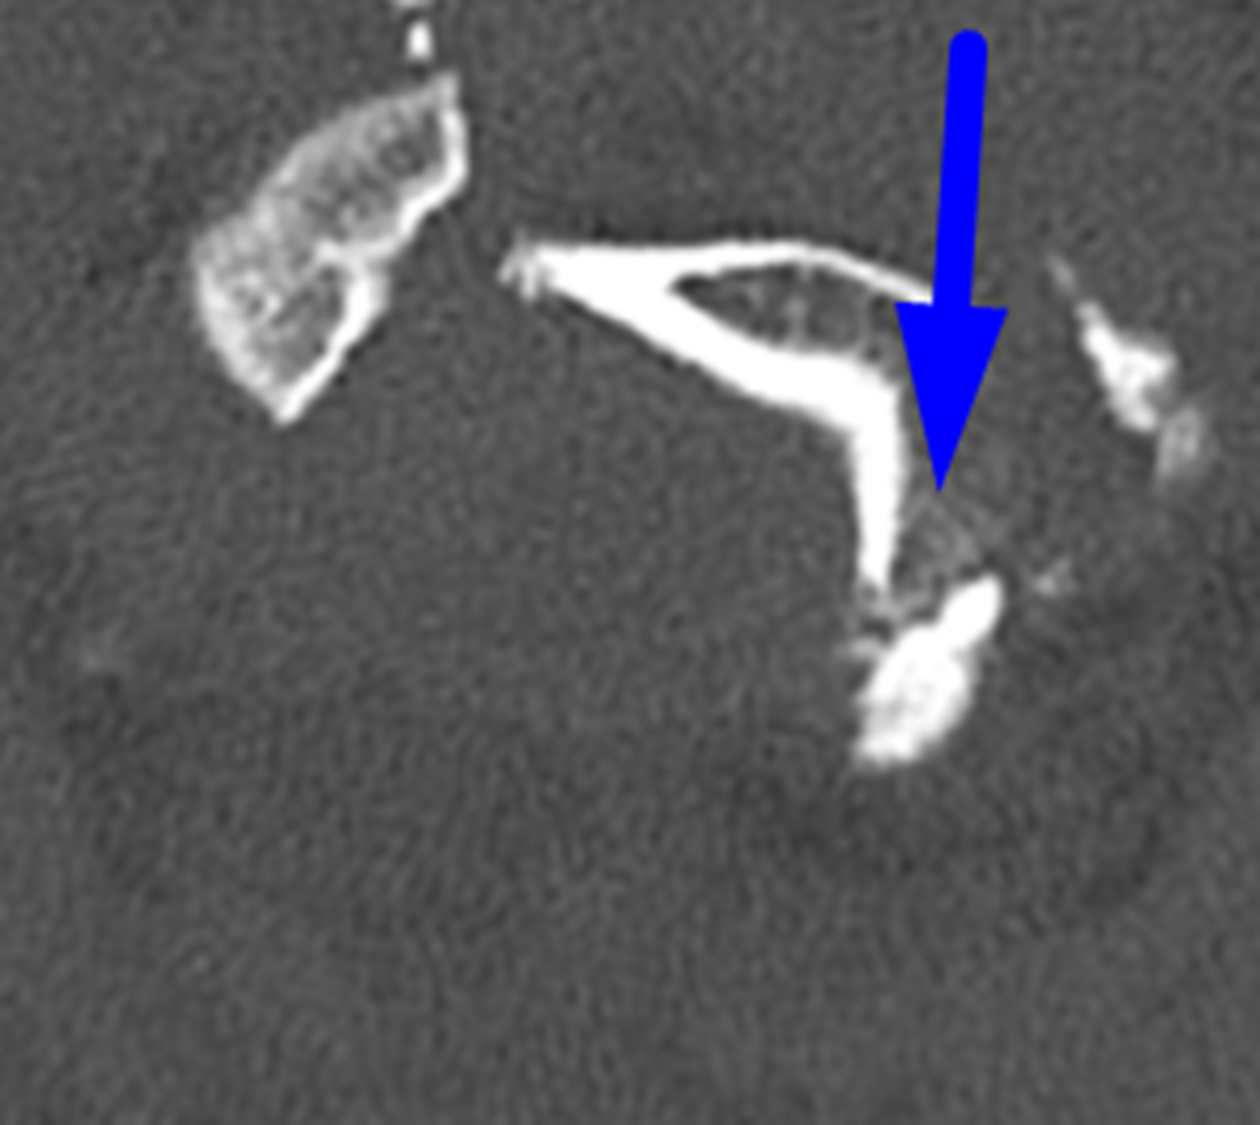

Blue arrow: displaced occipital condyle fracture.